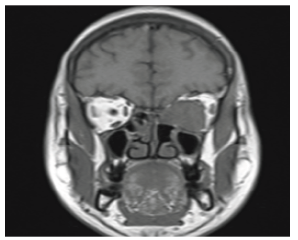

Magnetic resonance imaging (MRI) of the PNS and orbits (Figure 3) demonstrated an ill-defined, fusiform, t2 hypointense lesion with homogeneous enhancement involving the medial rectus muscle, with extensions suggestive of a pseudotumour The patient underwent endoscopic sinus surgery with excision of the intraorbital mass via Denker’s approach under general anaesthesia.3,4 The orbital mass was removed in toto and submitted for histopathological examination, which revealed features consistent with hyalohyphomycosis (Figure 4).